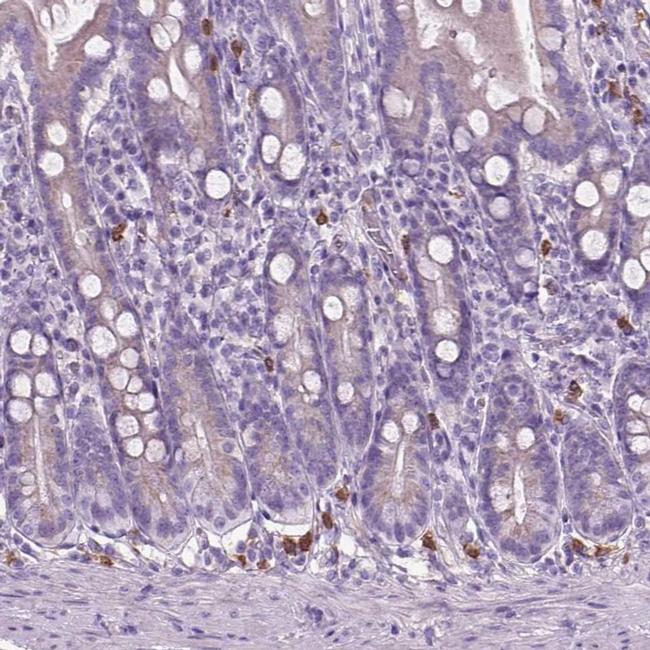

Immunohistochemical staining of CD84 in human small intestine shows strong cytoplasmic positivity in inflammatory cells. Samples were probed using a CD84 Polyclonal Antibody (Product # PA5-64444).